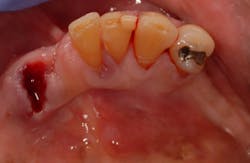

A 62-year-old African-American male presents for extraction of all remaining mandibular teeth, as well as placement of an implant-supported overdenture. At presentation, the patient’s health is noncontributory. The existing teeth have extensive periodontitis with a hopeless prognosis. Tooth No. 22 has Class III mobility and is removed prior to beginning treatment (figure 1).